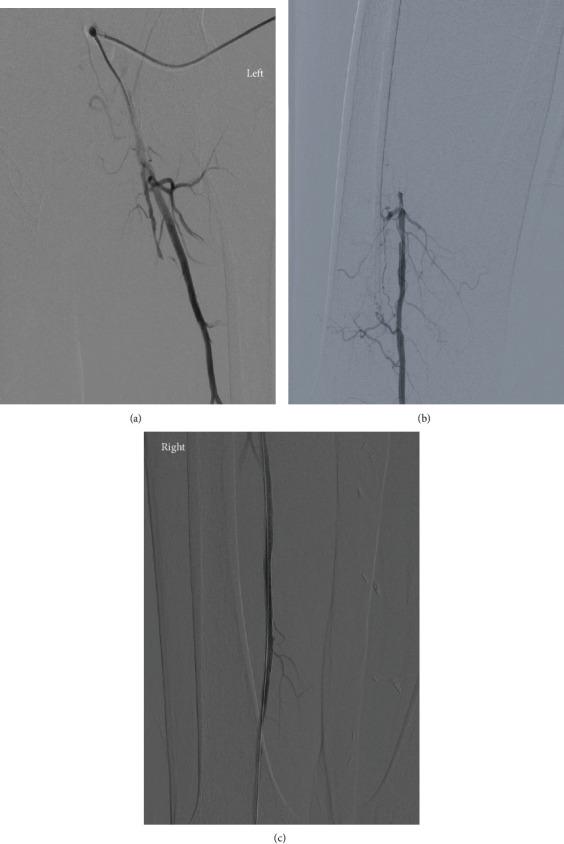

逆行腘动脉入路治疗复杂股浅动脉闭塞

Retrograde Popliteal Access for Challenging Superficial Femoral Artery Occlusion.

Retrograde popliteal access has long been established as an alternative to the antegrade approach to occlusive lesions in the superficial femoral artery (SFA). However, early reports with high complication rates (dissection, hematomas, aneurysms, and arteriovenous shunts at the puncture site) reduced enthusiasm for this technique. In recent years, with the development of thinner sheaths and low profile angioplasty devices, retrograde popliteal access has resurfaced as a viable technique, mostly in combination with or after failure of the more classical antegrade approach. In this retrospective study, we will report the safety and efficacy of the retrograde popliteal approach in the treatment of superficial femoral artery chronic total occlusions, in 13 consecutive patients between January 2017 and January 2021. The results showed 100% successful puncture of the popliteal artery and 100% successful recanalization and stenting of the superficial femoral artery with a total of 2 complications related to the puncture site and zero periprocedural mortality. In conclusion, the retrograde popliteal approach appears to be an effective and safe alternative to the common SFA complete total occlusion (CTO) treatment approach.

摘要